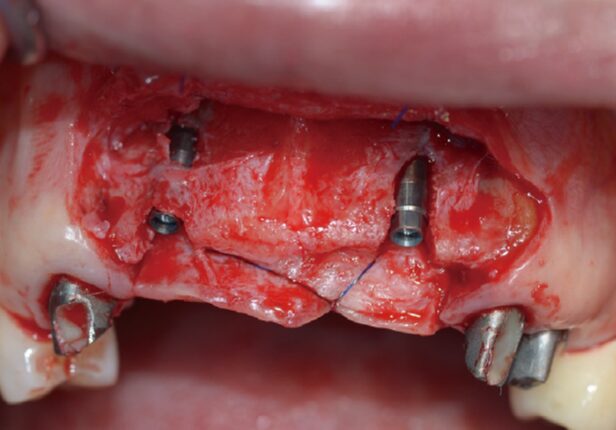

Implant placement